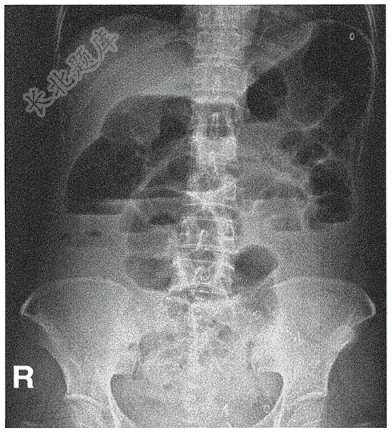

- 简答题患者男性,59岁,主因腹痛6小时就诊。查腹平片如下: